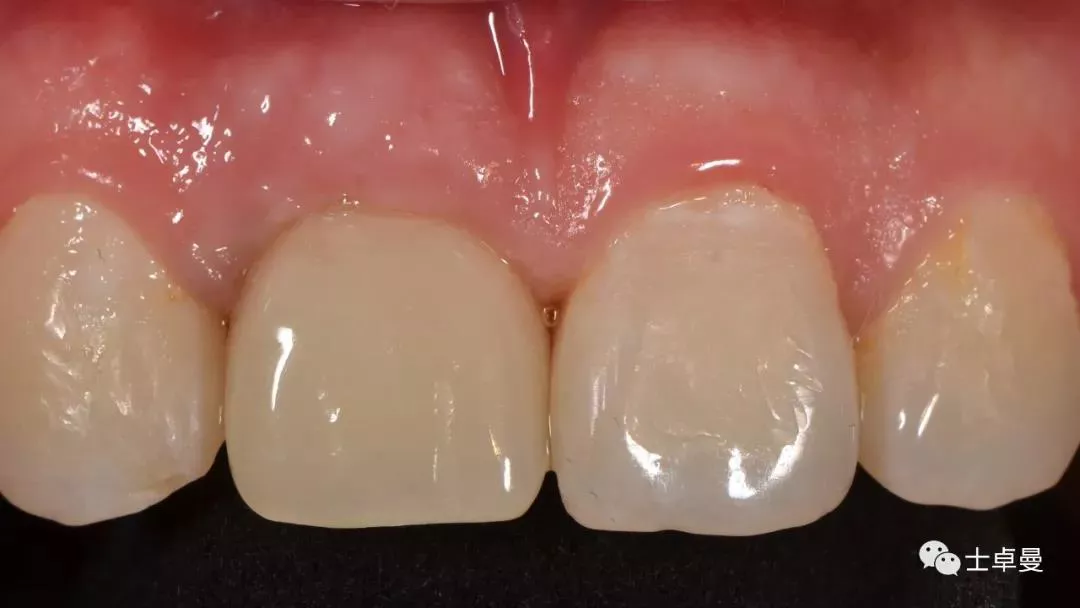

试戴种植体支持式临时修复体,塑型软组织

临时修复后2个月,龈缘及龈乳头位置理想,软组织健康

· 2个月后,见唇侧骨弓轮廓可,龈缘及龈乳头形态自然,去11临时修复体,植体ISQ值测定82,个性化取模,试戴Variobase氧化锆基台+LAVA氧化锆单冠,就位被动性良好,增加基台扭力至35Ncm,粘接固位上部冠,调合抛光。

完成永久修复,骨弓轮廓、龈缘及龈乳头形态自然,可见牙龈点彩,修复体外形及色泽可,患者满意。